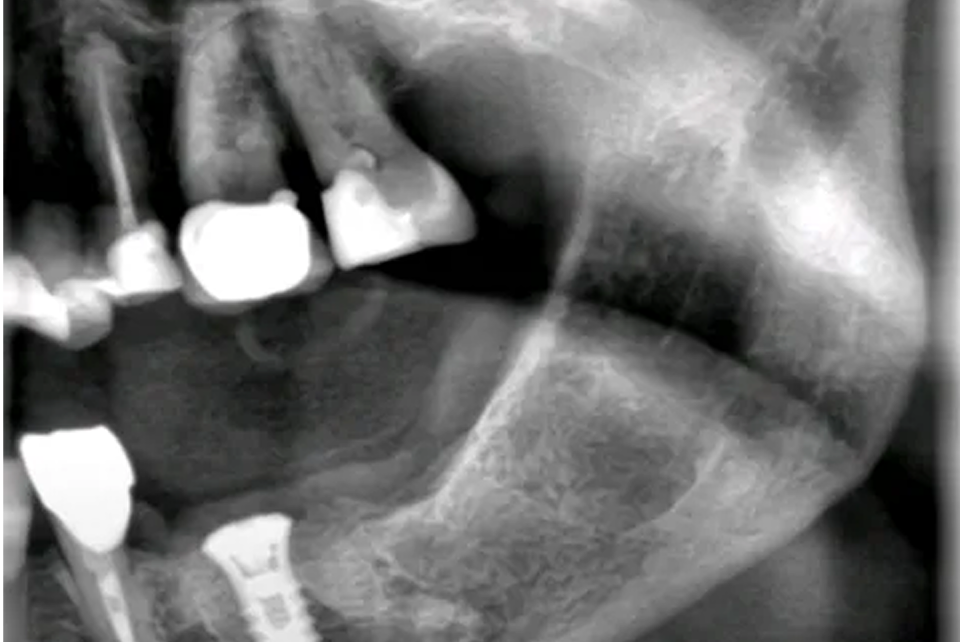

Direktimplantat efter tandutdragning – ett kliniskt exempel på när det lönar sig att vänta Direktimplantat efter tandutdragning är en behandlingsmetod som innebär att ett tandimplantat placeras direkt i alveolen efter att en tand tagits bort. När det används korrekt kan det ge mycket goda resultat med kortare behandlingstid och färre kirurgiska ingrepp. Men som med […]

En patientberättelse: Tre direktimplantat i överkäken – trygg och modern tandvård i Malmö Att förlora tänder innebär inte bara en praktisk utmaning i vardagen. För många påverkar det också självkänslan, talet, ansiktsprofilen och det sociala välbefinnandet. Samtidigt kan följderna för tuggningsfunktion och benvävnad vara långtgående. På Käkkirurgiskt Centrum Skåne träffar vi ofta patienter som söker en permanent […]

Direktimplantat efter tandutdragning – Så lyckades vi i ett svårt fall